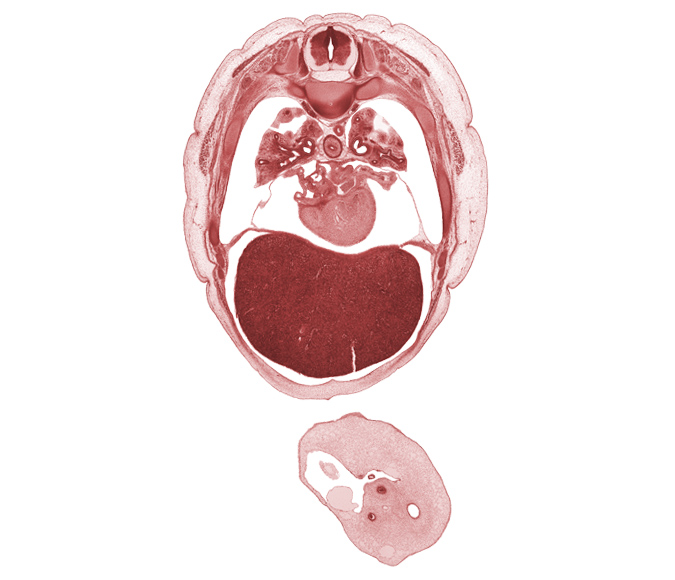

Carnegie Embryo #4090 | Location: 17-7

Keywords: T-5 spinal ganglion, artifact separation(s), caudal edge of scapula, head of rib 6, left lobe of liver, left upper pulmonary vein, lower lobe of left lung, middle lobe of right lung, neural arch, oblique fissure, pericardial cavity, pleural recess, right lobe of liver, secondary interatrial septum (septum secundum), trapezius muscle, umbilical coelom, umbilical cord, umbilical vesicle stalk, upper lobe of left lung

Source: The Virtual Human Embryo.